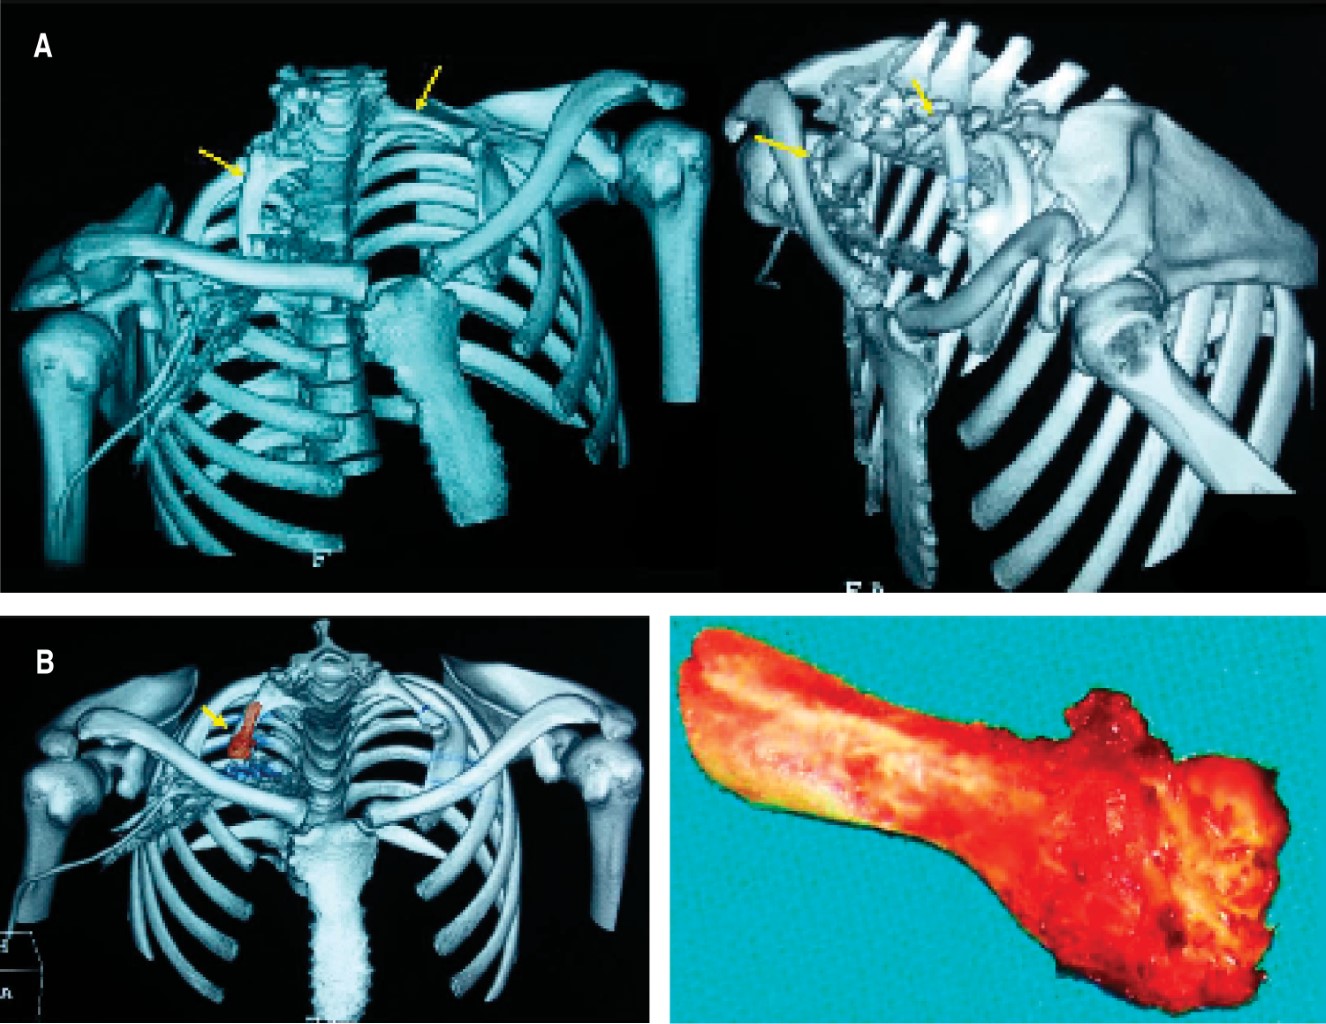

El estudio de electroconducción reveló disminución del reclutamiento de las fibras: 1o interóseo dorsal derecho, extensor del índice derecho, con normalidad de los grupos proximales del miembro superior al igual que el de los flexores y extensores comunes de los dedos, hallazgos de afección tronco inferior del PB derecho, el lado izquierdo no tuvo síntomas ni signos en el examen físico, la electroconducción indicó normalidad en el lado izquierdo. En imagen, la radiografía de tórax y tomografía demostraron costillas cervicales: derecha con el extremo distal libre y la izquierda con su extremo distal articulada en la cara posterior del tubérculo del músculo escaleno anterior de la primera costilla. En el estudio vascular de reconstrucción venosa se observó diminución calibre de la vena axilar derecha en el lugar del CONV (Figuras 1A, B, C y 2A).

Se realizó intervención quirúrgica, exéresis de CC y abordaje supraclavicular, se evidenció CC derecha articulada a la apófisis transversa C6, con borde libre estrechando el opérculo torácico (OCT), el tronco nervioso inferior del PB derecho se encontró comprimido y deformado, se realizó neurólisis, adherenciólisis del lugar del conflicto con trasposición, liberación del segmento comprimido y fresado del borde superior de la primera costilla (Figura 2B).

En el caso que presentamos, el paciente consulta por cuadro de cervicobraquialgia derecha con evidencia de neuropatía del tronco inferior del PB, la imagen demostró el lado derecho la costilla accesoria con borde libre, lugar del CONV (tipo II), mientras que el lado izquierdo sin sintomatología, la costilla accesoria tiene articulación verdadera con la primera costilla (Tipo I), el examen físico demostró con las pruebas de provocación compromiso vascular, por lo que revela un dato importante de SOCT arterial y neural.

Como mencionamos, según los hallazgos intraoperatorios se pueden observar distintas patologías que son concurrentes a la presencia de la primera costilla. Por lo tanto, se destacan procedimientos auxiliares como adherenciólisis y neurólisis del PB que se usan en presencia de bandas fibromusculares y ligamentarias anexas en casos de recidivas; en evidencia de tronco inferior deformado y desplazado son necesarias la liberación y la transposición neural, además se mencionan el fresado y exéresis parcial de la primera costilla.14-18 Por último, el compromiso vascular exige complemento de manejos tales como el endovascular y bypass vasculares para resolución de pseudoaneurismas y trombosis.9,17,18 En nuestro caso utilizamos el abordaje supraclavicular, realizamos exéresis de la CC en dos partes, la última incluyó la cabeza y parte la apófisis transversa vertebral, visualizamos las estructuras del PB indemnes, pero deformadas, por lo que procedimos a realizar adherenciólisis, liberación, neurólisis y transposición del tronco inferior para aumentar la posibilidad de éxito posoperatorio y evitar las recidivas (Tablas 1 y 2).